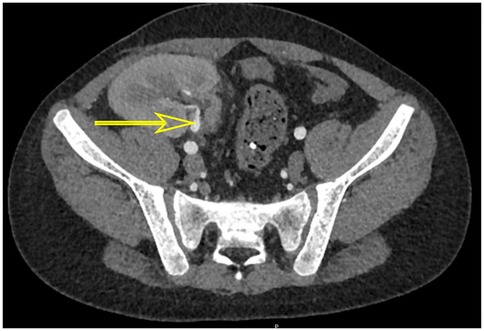

A case of cytomegalovirus-related hemorrhagic cystitis early after pediatric kidney transplantation

Cytomegalovirus (CMV) infections are commonly observed in immunocompromised patients. However, hemorrhagic cystitis (HC) is an exceptionally rare manifestation. Here, we report a pediatric kidney transplant recipient who developed CMV-related hemorrhagic cystitis, presenting with acute painful macrohematuria, blad